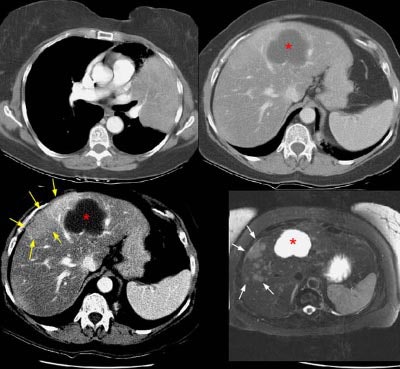

Example of Liver Metastases:

The patient below had an adenocarcinoma in the left lung that was obstructing the left upper lobe bronchus (left image upper row). The staging CT scan demonstrated a large liver cyst (*) and some underlying hepatic heterogeneity best appreciated on liver windows (yellow arrows). The patient had slightly elevated liver function tests, and the findings were felt to be most likely related to areas of sparing in a patient with some hepatic fatty infiltration. Because the possibility of metastatic disease could not be excluded, an MRI of the liver was performed. The heavily T2-weighed image shown (right image bottom row) revealed multiple liver metastases, many of which were not apparent on the contrast-enhanced CT scan (white arrows). MR imaging has been shown to be more sensitive for detecting liver metastases when compared to CT.